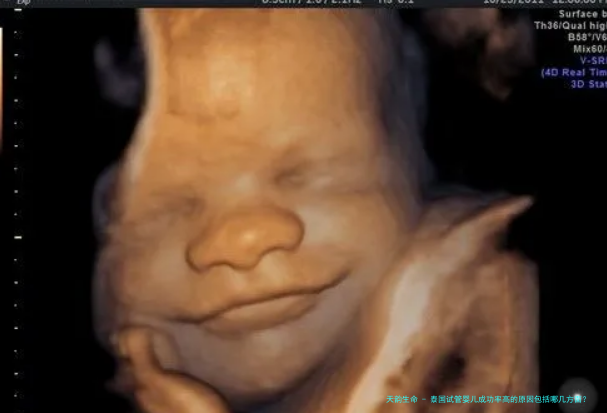

泰国试管婴儿成功率高的缘由包括哪几方向?体外受精-胚胎移植技术距离现在已经有几十年的历史了。生殖专家将试管婴儿技术视为现代医疗科技的1个奇观。同一时间泰国也被认为是世界上试管婴儿技术相较发达的国家之一。在泰国,试管婴儿的成功率可以达到70%。那泰国试管婴儿成功率高的缘故是哪几方向?

泰国的试管婴儿医院,拥有世界先进的胚胎实践室和世界尖端的医疗设备。通常情况下,受精卵是在输卵管内结合的,受精卵通过输卵管纤毛的蠕动功能将受精卵送入子宫,实现着床发育。而泰国的试管婴儿技术是利用先进的医疗设备,将精子和卵子分别拿出来之后,在特定的环境下完成受精,然后发育成胚胎,最后移植到女性的子宫内继续发育。

能够发育成囊胚的胚胎,都是质量较好、着床率较高、容易发生妊娠反应的胚胎。从培育受精卵开始直至受精卵发育到第4天,细胞破裂的速率会急遽加速,泰国的生殖专家们会随时监测胚胎的发育情况,并对培育液中的气温、营养、密集度做出最适当的处置,以保证一个健康的受精卵顺利存生存到第五日,成为高质量的囊胚。